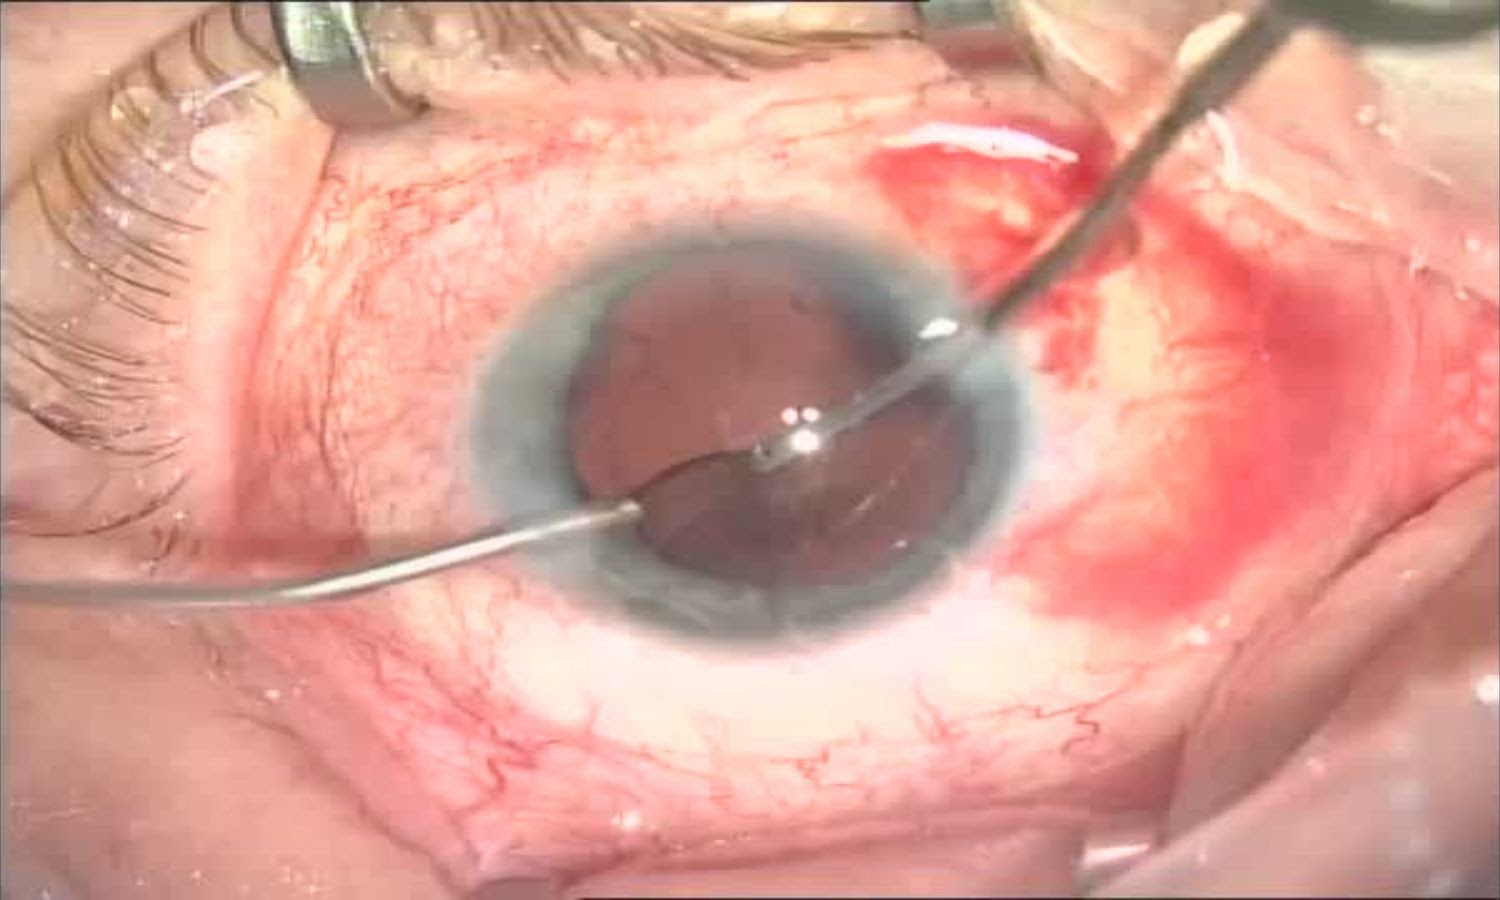

В пинцете — первая линза, которую сворачивают в трубочку и помещают в одноразовый инжектор:

Далее в сделанный ранее основной прокол вставляется инжектор, который вводит линзу в освободившееся пространство. Под силами собственной упругости (и обладая памятью формы) линза разворачивается, а её «лапки» упираются в края капсулы хрусталика. Чем лапок больше, тем лучше. Чем меньше свободного пространства остаётся в мешке — тем тоже лучше.

Дальше задача хирурга — правильно сориентировать линзу по оси вращения. Спустя какое-то время линза окончательно «сядет», а форма капсулы хрусталика надёжно «обнимет» её. Затем вымывается вископротектор из-под линзы (и над ней) иии готово.